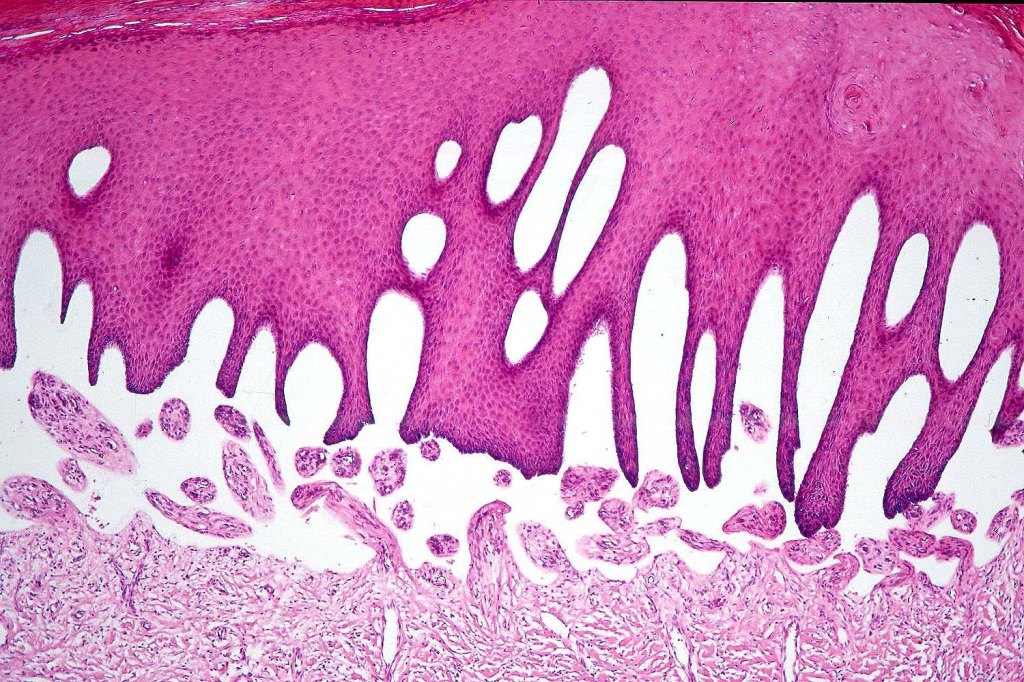

Histological features

•Generally, tumors are well differentiated although they can later develop a more poorly differentiated morphology

•Keratoses may represent a precursor & sometimes histological distinction between very marked epidermal hyperplasia (pseudoepitheliomatous) and early SCC can be problematical (personal observation)